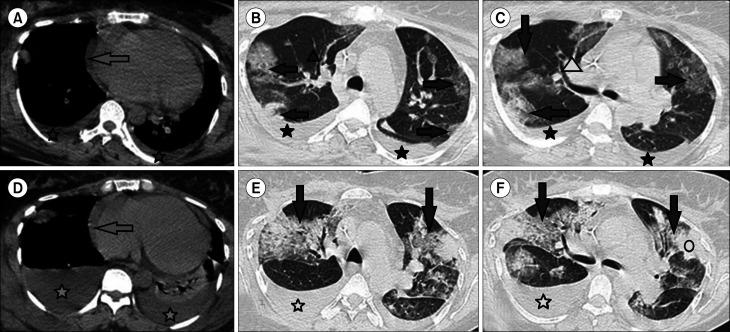

Data on the association between coronavirus disease 2019 (COVID-19) and the epidemiology and outcomes of hematological malignancies are limited. Hence, the present study aimed to assess the imaging findings using chest multidetector computed tomography (MDCT) in patients with hematologic malignancies who developed COVID-19 pneumonia.

This retrospective study included two groups, the first group consisted of COVID-19 infected patients with hematologic malignancies (100 patients), while the second group consisted of COVID-19 infected patients without hematologic malignancies or other comorbidities (100 patients). The hematological malignancies included in this study were non-Hodgkin's lymphoma (40 patients), acute myeloid leukemia (25 patients), chronic lymphocytic leukemia (15 patients), multiple myeloma (10 patients), Hodgkin's lymphoma (8 patients), and myelodysplastic syndrome (2 patients). Chest multidetector CT imaging was performed in all patients to assess for ground-glass opacity, consolidation, pleural effusion, and airway abnormalities.

More than one CT finding was reported in each patient. No significant difference was observed in the ground-glass opacities (=0.0594), nodule formation (=0.2278), or airway thickening/dilatation (=0.0566) between the two groups; meanwhile, a significant difference was observed in the degree of consolidation, the number of lobes affected, and pleural effusion (=0.0001) as well as in the total lung severity (=0.0001); minimal, mild, and severe affection rates; and (=0.0047) moderate affection rates.

Early and reliable diagnosis of lung disease in COVID-19-infected patients may be achieved through multidetector CT imaging. Patients with hematological malignancies are more likely to have severe COVID-19 pneumonia, and radiologists should recognize the CT characteristics of this infection.